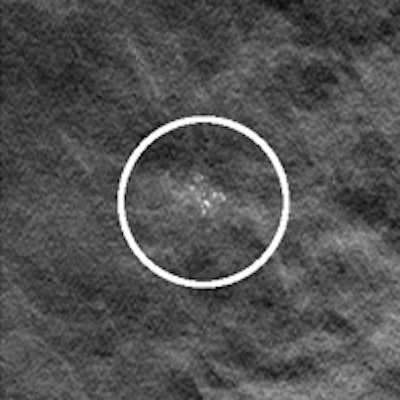

Left: Example of a breast tomosynthesis slice holding a simulated mass. Right: Example of a breast tomosynthesis slice holding a simulated microcalcification cluster. All images courtesy of Dr. Pontus Timberg.Image volumes can be viewed using free scroll volume browsing (FS) or in a cine loop. The standard procedure is FS, but in clinical practice observers often use a cine loop to get an overview of the images. In addition, breast tomosynthesis images may be displayed on the monitor in either vertical or horizontal orientation. The researchers evaluated the efficiency of several breast tomosynthesis image volume readings using an experimental setup. They assessed these in terms of lesion detection performance, time efficiency, visual attention, and search using jack-knife alternative free-response receiver operating characteristics (JAFROC) and eye tracking.

The researchers selected 55 normal breast tomosynthesis cases in mediolateral oblique view, which were then verified by an expert radiologist panel. The exams were acquired with a Siemens Mammomat Novation BT prototype (Siemens Healthcare). All viewing procedures consisted of FS, and three were combined with initial cine loops at three different frame rates (9, 14, and 25 fps). The presentation modes consisted of vertically and horizontally orientated image volumes.